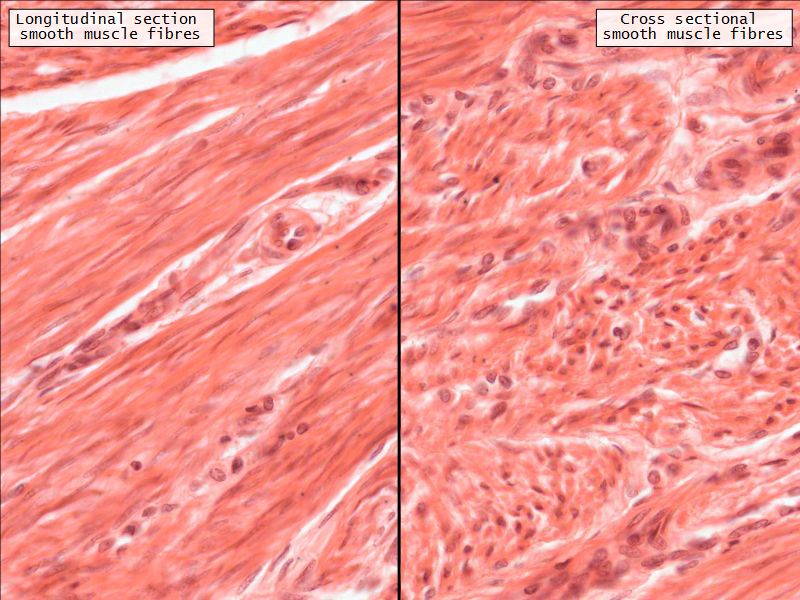

Myometrium

- 3 layers indistinct smooth

- Inner longitudinal/oblique

- Central circular

- Large blood vessels

- Stratum vasculare

- Outer longitudinal/oblique